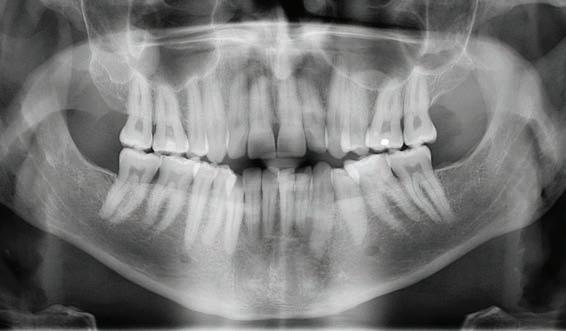

The panoramic radiograph (Figure 3) highlights the three missing premolars and absence of all third molars. Root length is excellent and periodontal support is good. The patient’s restorative index is low, a reflection of his history of regular dental care and good oral hygiene. The cephalometric radiograph, and analysis (Figure 4a and 4b) suggest a near-Class I skeletal relationship with mildly increased skeletal vertical dimension (MPA 35.8). Mandibular incisor angulation is significantly below average (IMPA 84.7), relative to the steeper than average mandibular plane. Visually, incisor angulation appears to be normal.

Figure 3: INITIAL panoramic radiograph Figures 4a and 4b: Initial cephalometric radiograph and analysis